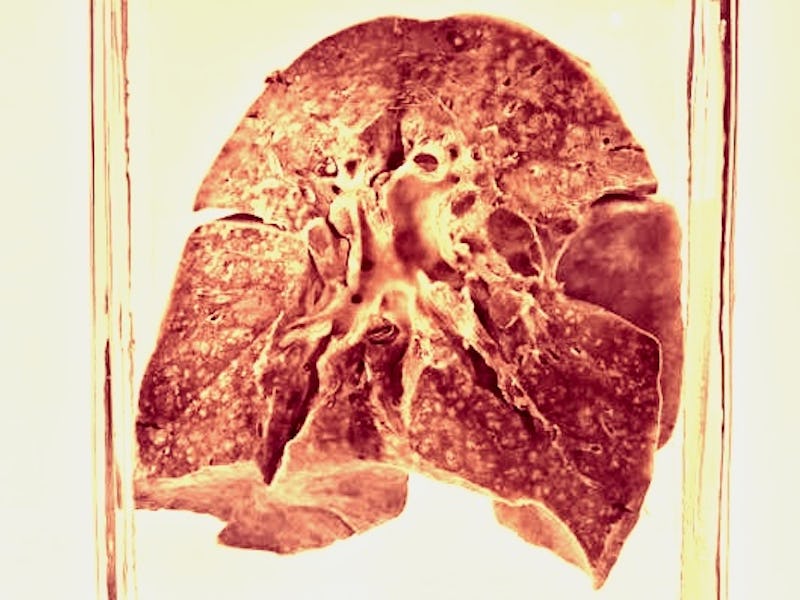

Preserved lungs from 1912 have pushed back the emergence of measles by 1,500 years.

The lungs were originally collected during an autopsy after their original owner died of measles-related bronchopneumonia on June 3, 1912, according to the paper’s supplementary material. Then, they remained untouched for over a century.

As Science magazine reported, these lungs were found by the study’s senior author Sébastien Calvignac-Spencer in a basement at the Berlin Museum of Medical History. That museum is already known for a collection of organs suspended in jars, reminiscent of Snape’s potion classroom.